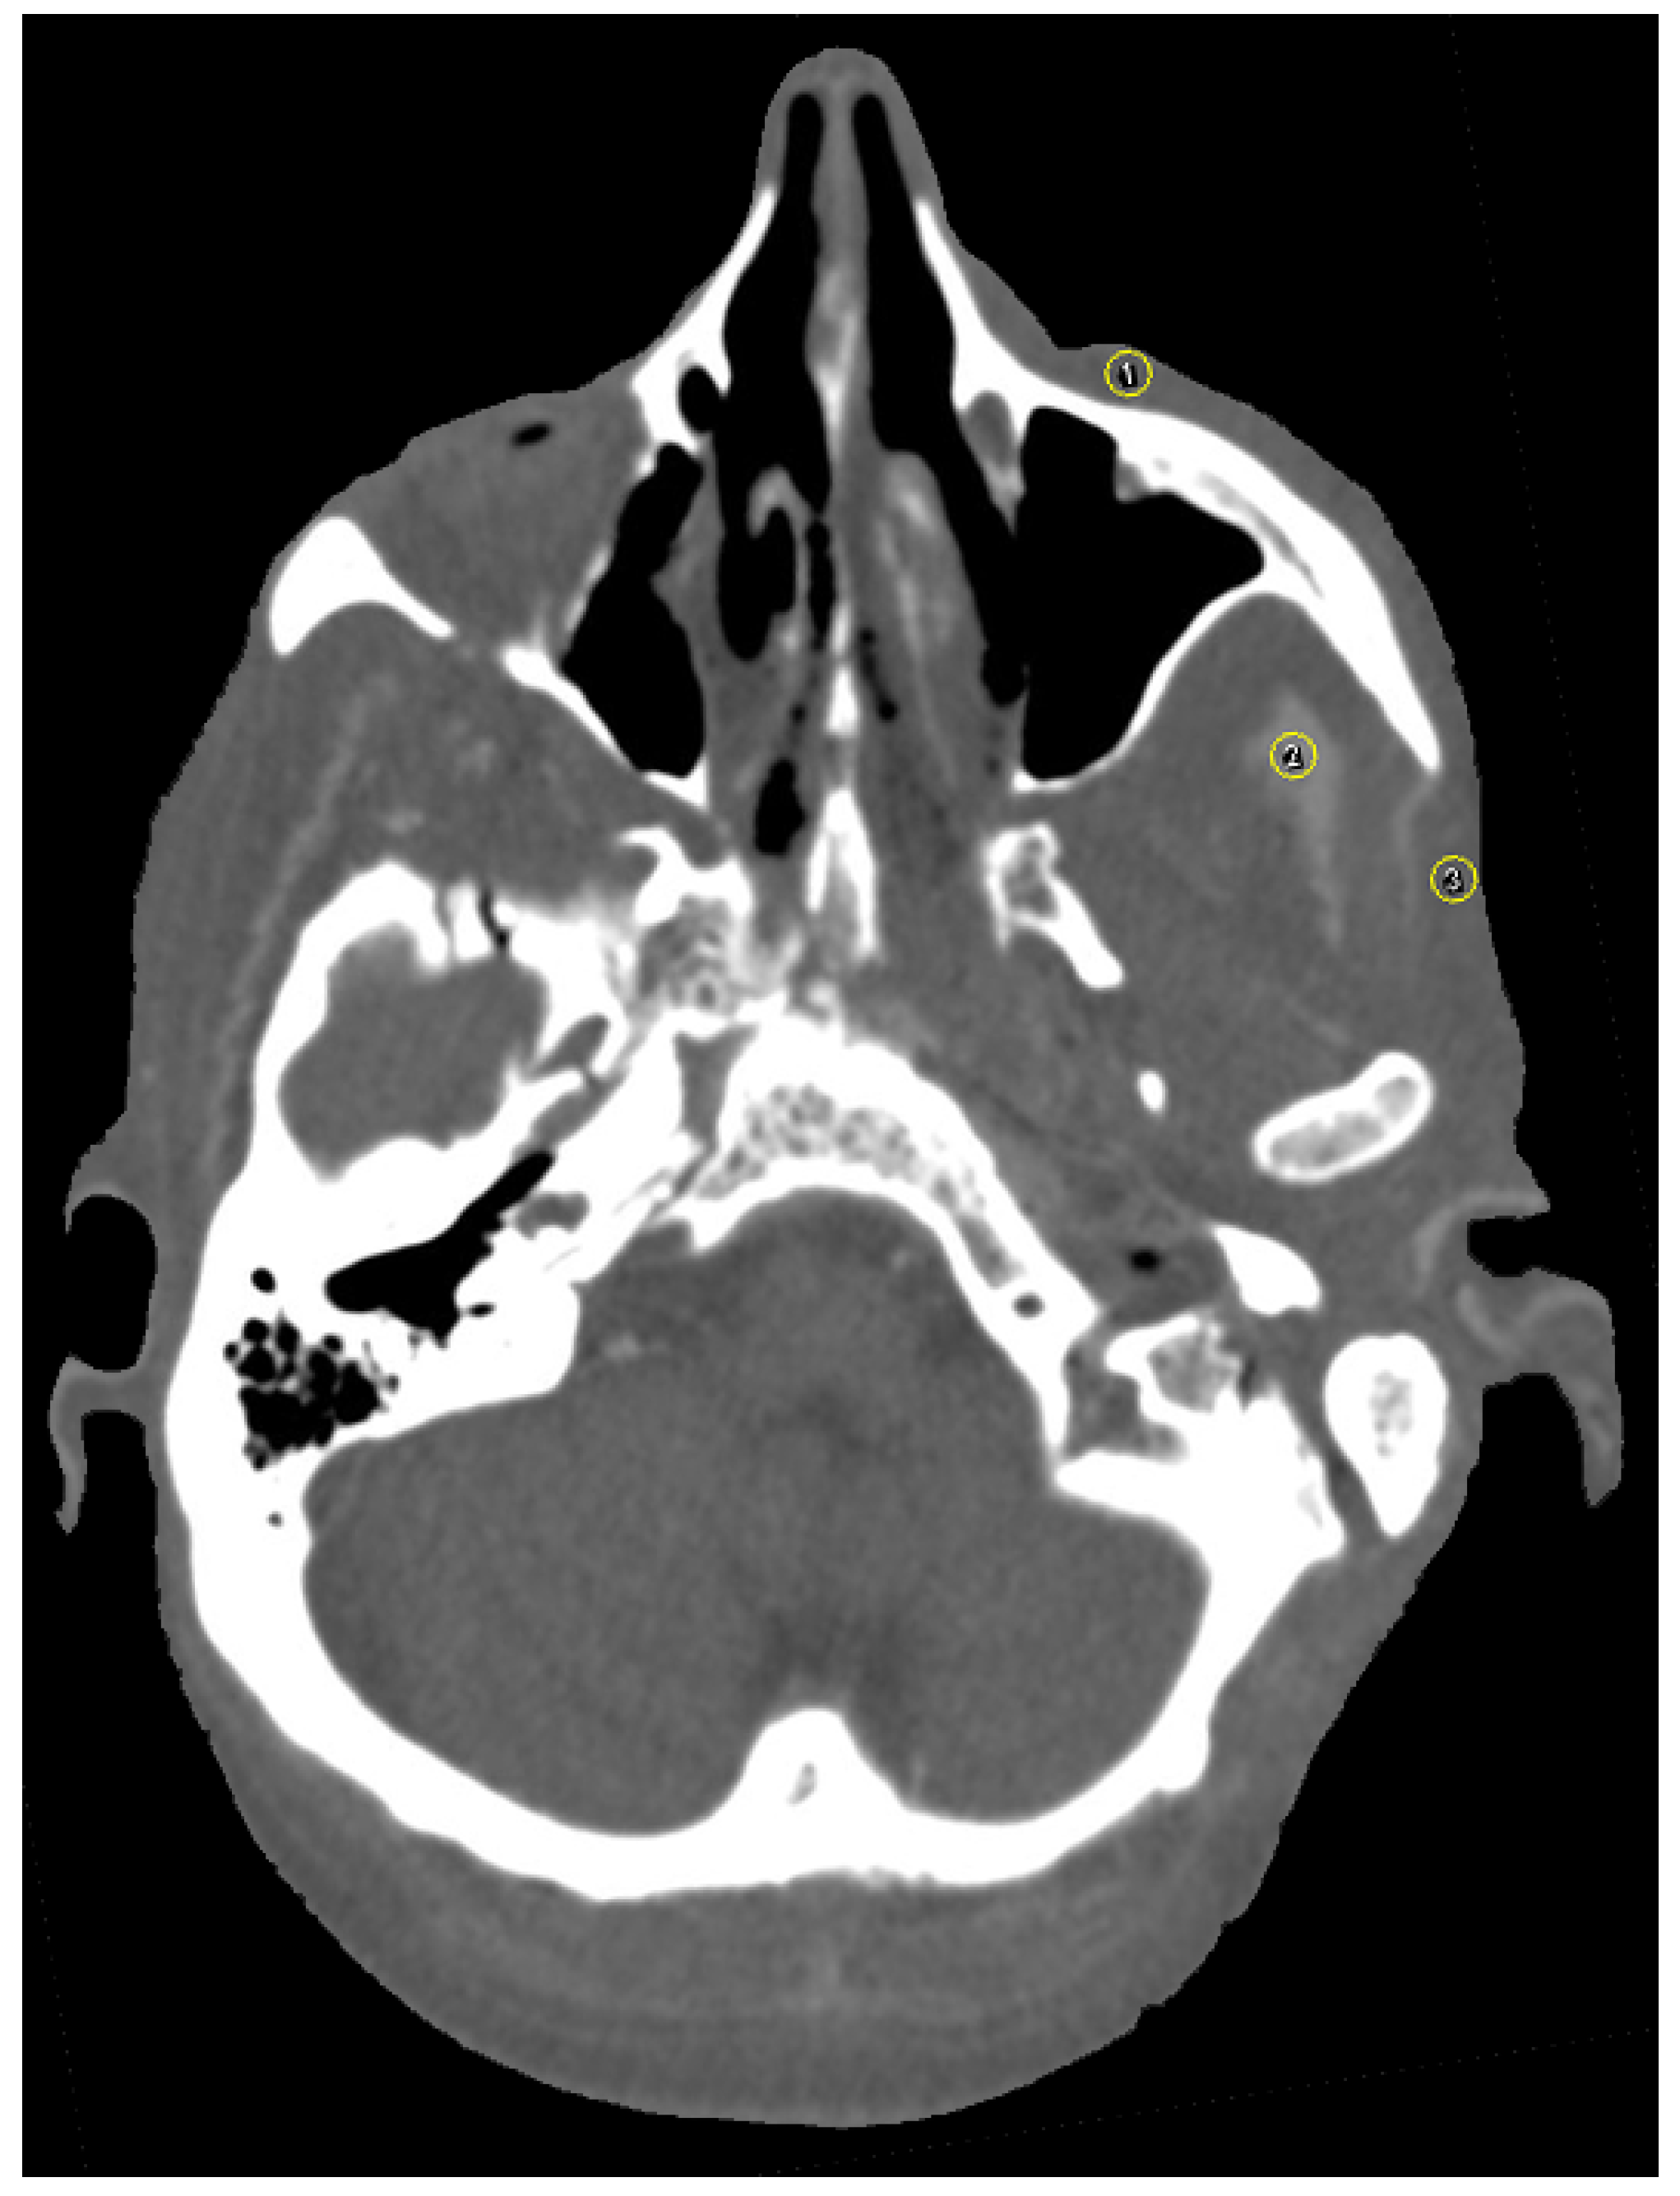

2.7. Image Analysis

3.1. Streak Artifacts

3.1.1. Implant Material